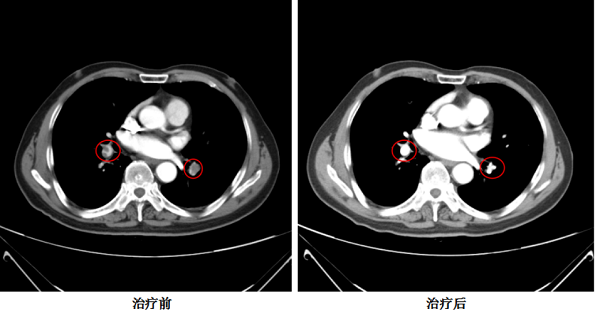

1月后,患者复查胸部增强CT提示原肺动脉内栓子基本消失,右下肢血管彩超提示腘静脉血栓伴部分管腔再通,目前病情稳定,顺利完成两程全身化疗。